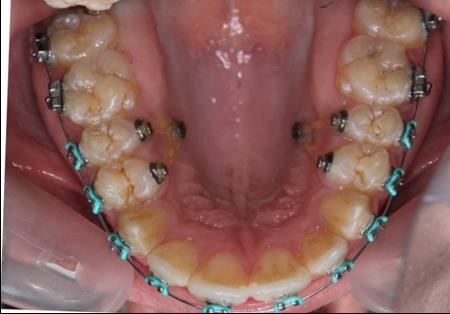

In this case the implants were loaded after one week with a 100-150 force using an elastic chain.

The intrusion rate obtained was 0,5-1 mm per month without root resorbtion or vitality problems.

Figure 5.Intraoral photography after the mini-implant activation